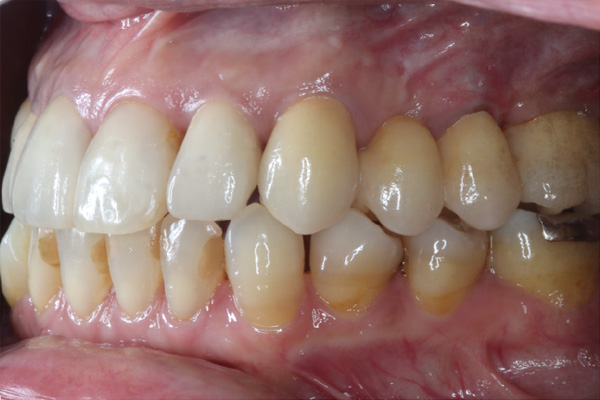

| 年代・性別 | 50代 男性 |

|---|---|

| 主訴 | 右上下の歯が痛い |

| 治療期間 | 約12ヶ月 |

| 費用 | 2,500,000円 |

| 治療内容 | インプラント、骨造成、結合組織移植、セラミック修復 |

| 治療に伴うリスク | インプラント周囲炎 セラミックの破折、脱離 |